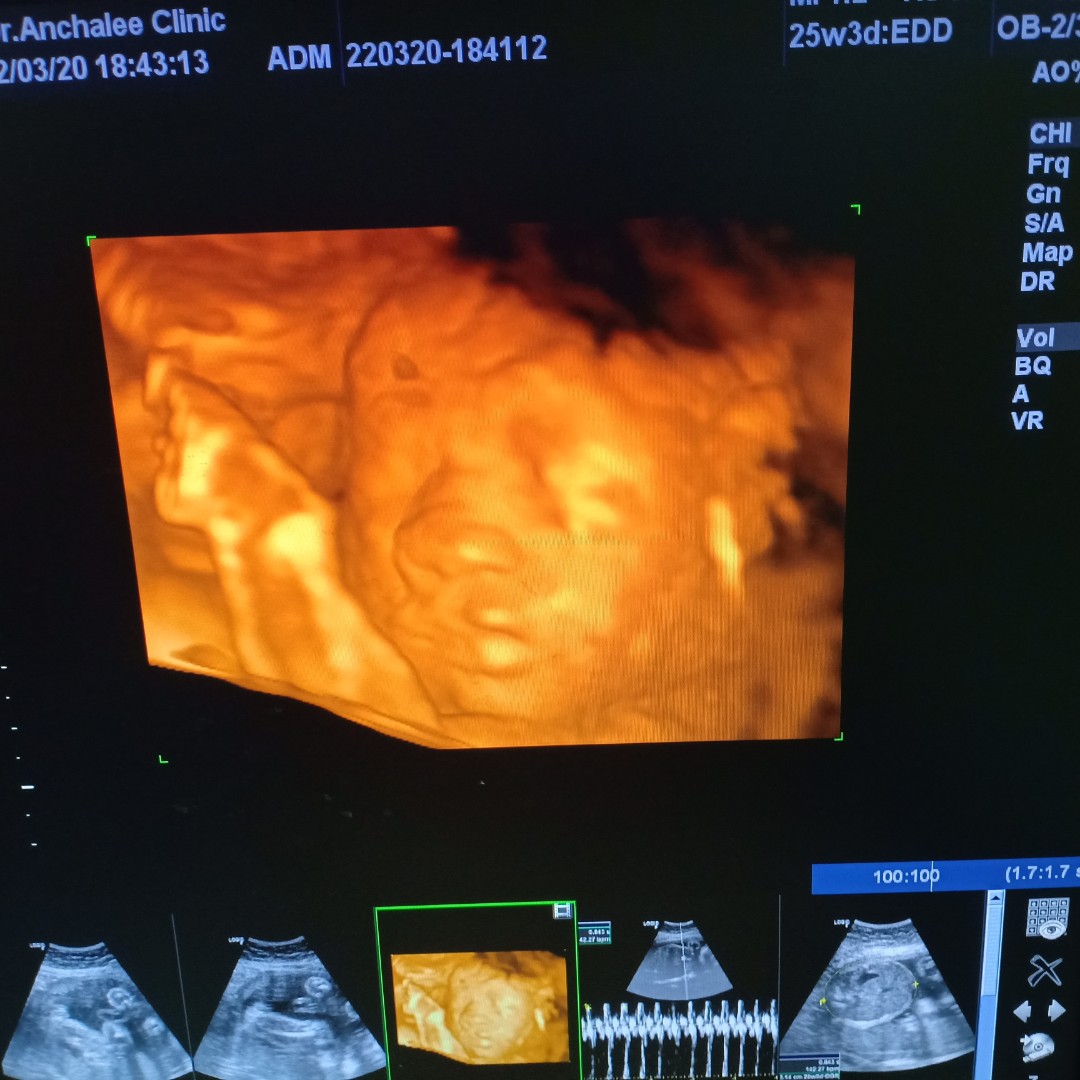

เห็นหน้าชัดกันมั๊ยคะ บ้านนี้ เอามือบังตลอดเลยค่า หมอเขย่าท้องก็แล้วไม่เอาออกเลยย ??

ตอน นั้นประมาณ6เดือน..ตอนนี้36wแล้ว

บ้านนี้เอามือปิดแบบนี้เลยจ้า555